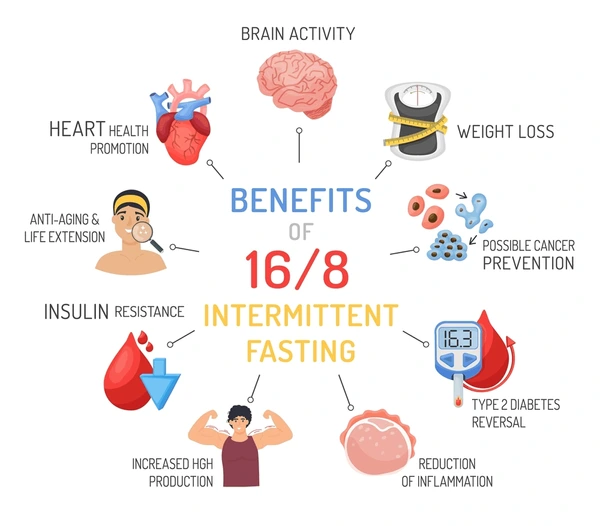

इंटरमिटेंट फास्टिंग : इंटरमिटेंट फास्टिंग में दिन को दो हिस्सों में बाँटा जाता है—फास्टिंग (उपवास का समय) और ईटिंग (भोजन का समय)। सबसे सामान्य तरीका है 16:8, यानी 16 घंटे उपवास और 8 घंटे में भोजन। इसका उद्देश्य शरीर को आराम देना, वजन कम करना और मेटाबॉलिज़्म सुधारना होता है।

इंटरमिटेंट फास्टिंग क्या है?

एक समय आधारित उपवास — 16 घंटे उपवास + 8 घंटे भोजन = 16:8 Method यह पाचन तंत्र को आराम देता है, ठीक वैसे जैसे मशीन को रेस्ट देने से उसकी उम्र बढ़ती है। इसीलिए स्वास्थ्य और आध्यात्मिकता दोनों के लिए उपवास क्यों ज़रूरी है — इसका स्पष्ट कारण मिलता है।